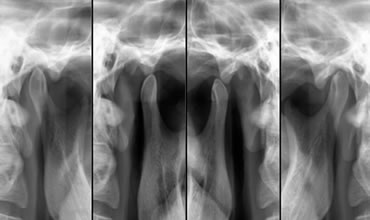

ATM

Dor na articulação temporomandibular. Dores na musculatura da face e da cabeça. Problemas de oclusão dental